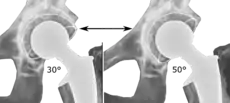

Post-operative projectional radiography is routinely performed to ensure proper configuration of hip prostheses.

The direction of the acetabular cup influences the range of motion of the leg, and also affects the risk of dislocation.[9] For this purpose, the acetabular inclination and the acetabular anteversion are measurements of cup angulation in the coronal plane and the sagittal plane, respectively.